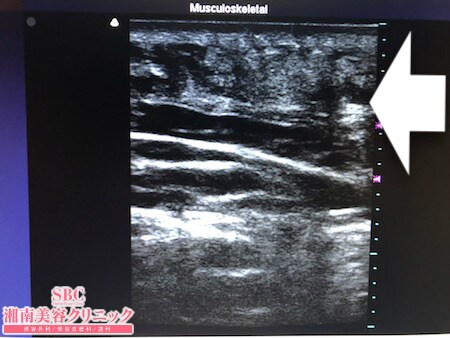

No.226821【脂肪吸引】【動画あり】湘南美容外科脂肪吸引最高責任者である竹田先生による脂肪吸引のフォトギャラリー!10年前の再手術!取り残しを気にして早10年!ここは最後に根こそぎ竹田先生に根こそいでもらう!!術中3Dタッチビュー・右肩甲骨横

背中は

肩甲骨横

ブラジャーの上下

の皮下脂肪を取ることを目的にしています。

背中の皮下脂肪は硬く線維質で

脂肪吸引が難しい部位です。